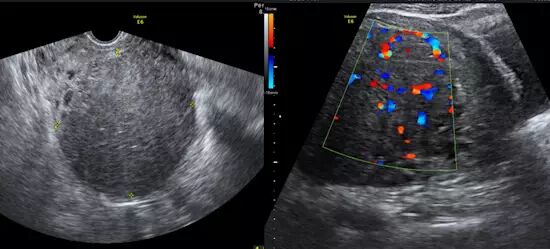

图 1 为 34 岁女性,经量过多,经期为 9 天,同时患有二尖瓣狭窄。超声发现一 10*8 cm 子宫肌瘤,接受肌瘤栓塞术